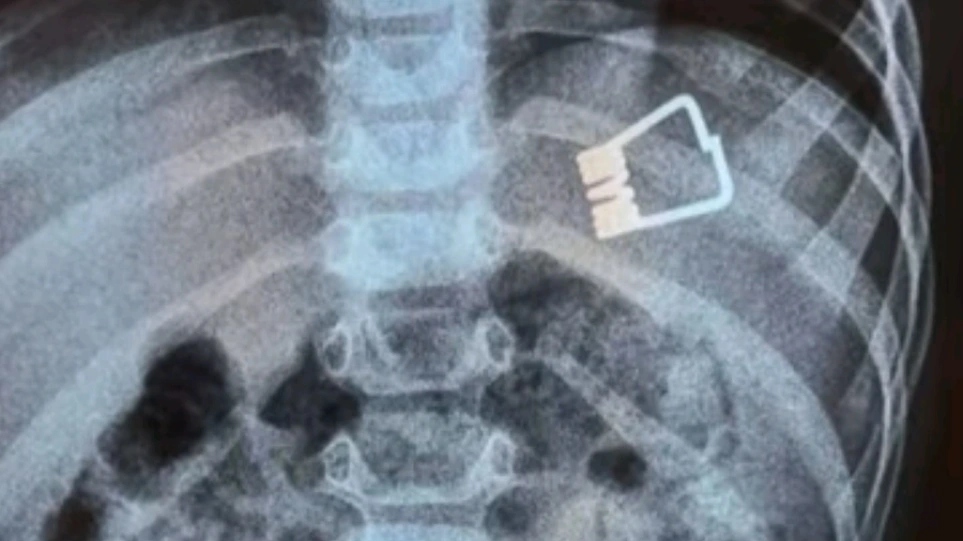

Ένα απίθανο συμβάν έλαβε χώρα στην Λήμνο όταν ένα αγοράκι μόλις 2 ετών κατάπιε ένα μανταλάκι και χρειάστηκε να διακομιστεί στο Ιπποκράτειο Νοσοκομείο στη Θεσσαλονίκη.

Εκεί, οι γιατροί κατάφεραν να βγάλουν το μανταλάκι από τον οργανισμό του παιδιού χωρίς χειρουργική επέμβαση, αλλά με τη βοήθεια ενός ενδοσκοπίου τελευταίας γενιάς.

Σύμφωνα με το ρεπορτάζ της ΕΡΤ, το παιδί κατάπιε το μανταλάκι στο σπίτι του και στη συνέχεια μεταφέρθηκε με Super Puma από τη Λήμνο στη Θεσσαλονίκη, όπου το ανέλαβαν οι παιδίατροι.

«Όταν το παιδί έφτασε εδώ αμέσως κινητοποιηθήκαμε, ενημερώσαμε τους αναισθησιολόγους, είχαμε έτοιμο το χειρουργικό κρεβάτι. Το παιδί έπρεπε είναι νηστικό 6 με 8 ώρες και προβήκαμε στην αφαίρεση ενδοσκοπικά του ξένου σώματος», δήλωσε ο Ιωάννης Ξηνίας, αναπληρωτής καθηγητής Παιδιατρικής Γαστρεντερολογίας.

Το παιδί επέστρεψε στη Λήμνο και είναι καλά στην υγεία του.